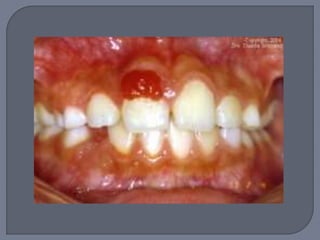

Lesión elevada localizada de tejido de

granulación

Masa exofítica a veces lobulada y ulcerada

Por lo general pedículada

Color rojo o rojo púrpura

Tendencia a sangrado

Diámetro de milímetros a centímetros

Cuando se da durante el embarazo se le llama

“ tumor del embarazo” o “ épulis del

embarazo” o “granuloma gravídico”

Suele iniciar en el primer trimestre y va

creciendo

Sobre todo si es pequeño desaparece después

del parto

En algunas ocaciones se extirpa por razon funcionales

o estéticas o por sangrado frecuente